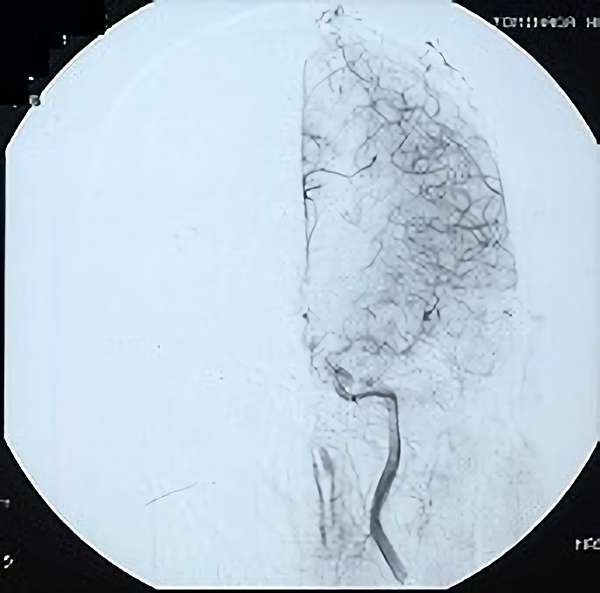

脳血管撮影

手術前

手術後